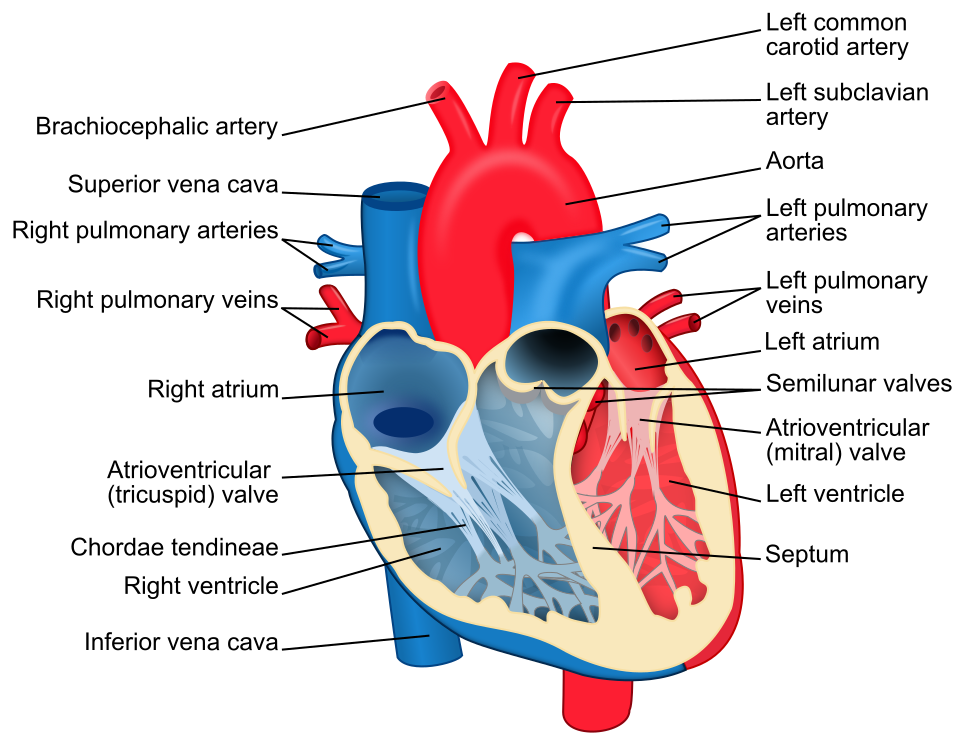

Figure 1 - Canine heart anatomy diagram showing all four cardiac valves - mitral, tricuspid, aortic, and pulmonic - with labeled chambers.